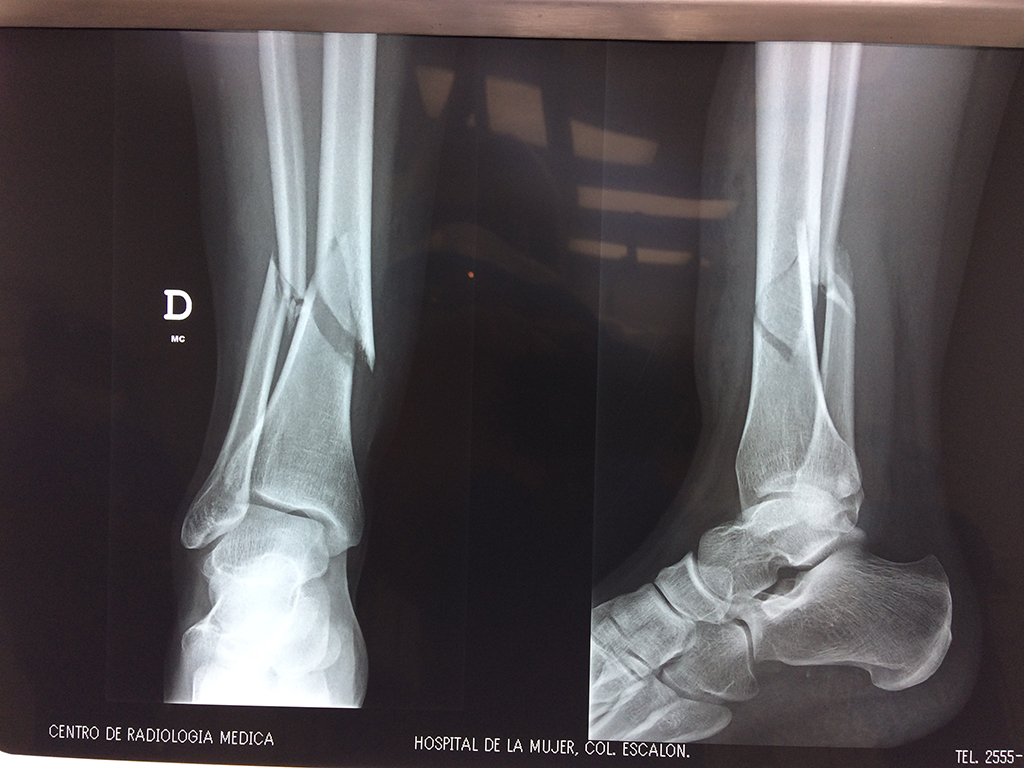

Aunque cada uno de estos huesos puede fracturarse por separado, normalmente la rotura es una lesión que se produce de forma conjunta

La mayor parte de las roturas implican a la parte proximal del hueso (parte del hueso próximo a la rodilla) o a la parte distal (parte del hueso cerca del tobillo).

Debido a la fina cobertura de piel que recubre la tibia y el peroné, las fracturas generalmente son abiertas, es decir, el hueso roto rasga la piel, atravesándola. Las fracturas de tibia y peroné generalmente se producen por un fuerte impacto o torsión.